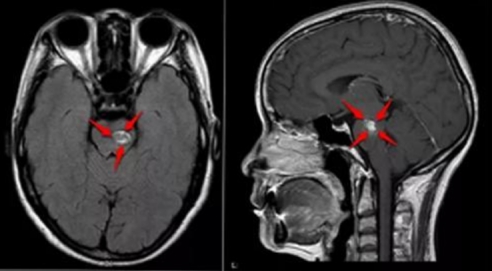

巴特朗菲教授脑干海绵状血管瘤经典案例